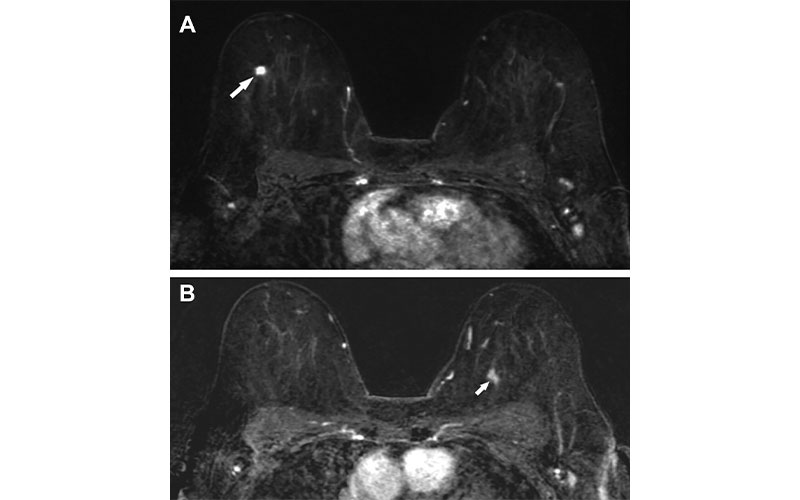

Axial, fat-saturated, contrast-enhanced, and subtracted T1-weighted MRI scans in a 65-year-old woman with newly diagnosed breast cancer show (A) a 0.7-cm irregular homogeneously enhancing mass in the upper outer right breast (arrow) and (B) contralateral disease detected only with MRI as a 1.2-cm area of nonmass enhancement in the upper inner quadrant (arrow). After bilateral lumpectomy with sentinel lymph node biopsy, the final pathologic examination showed bilateral invasive ductal carcinoma, histologic grade I, with negative lymphovascular invasion, positivity for estrogen and progesterone receptors, and negativity for human epidermal growth factor 2 receptor; both were negative for axillary node disease. The patient underwent radiation therapy and then endocrine therapy for 5 years, with no evidence of local or distant recurrence 11 years after treatment.